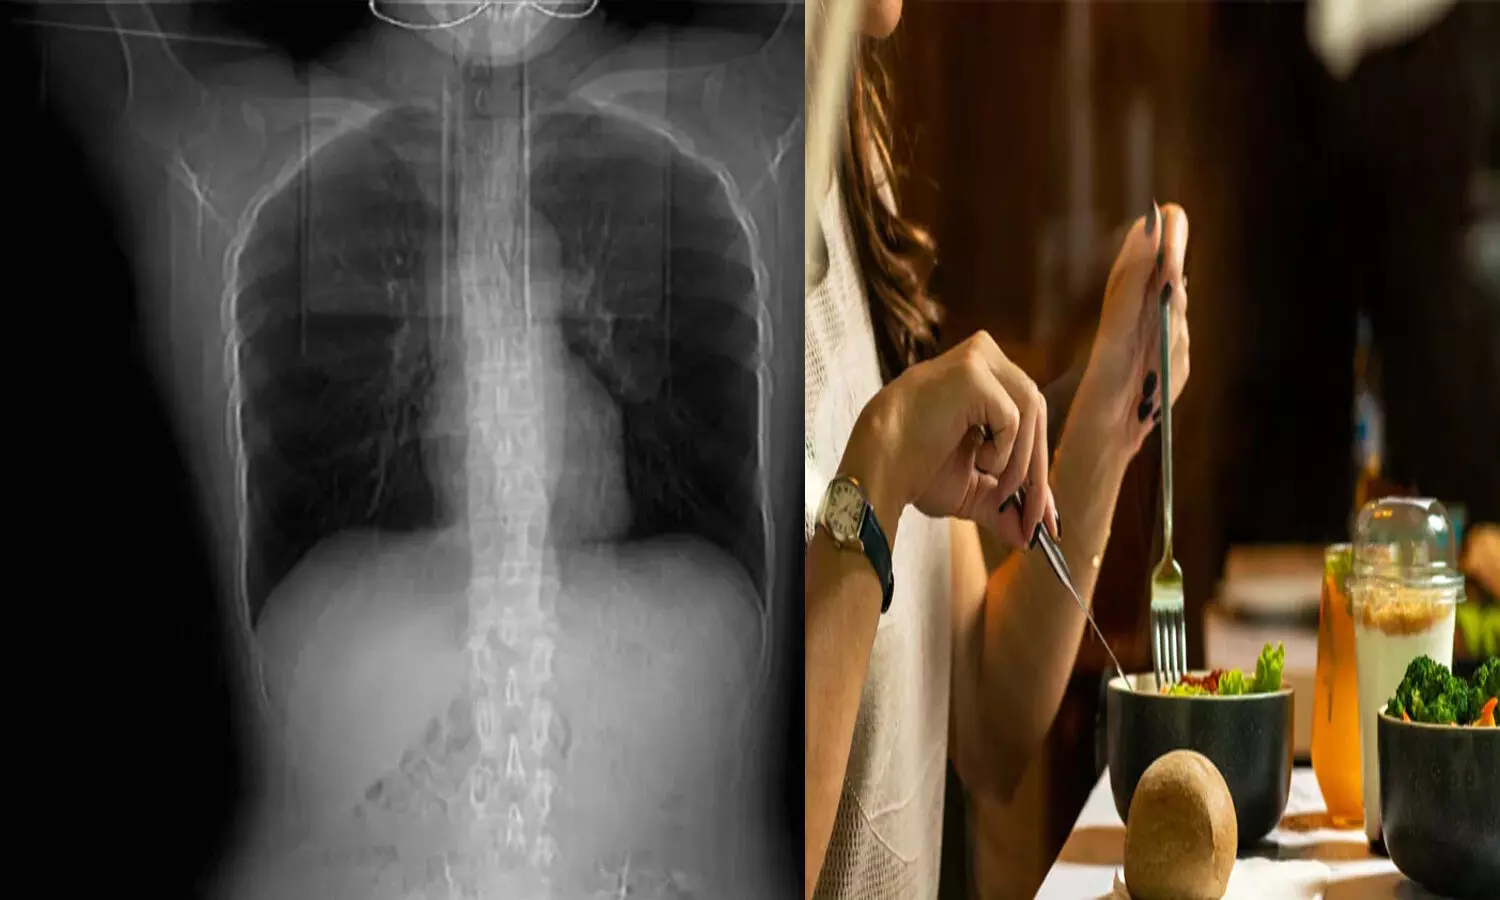

ఆ తర్వాత నొప్పి పెరగడంతో.. వైద్యులను సంప్రదించింది. స్కానింగ్ చేసిన వైద్యులు ఛాతీలోని నాలుగు పక్కటెముకలు విరిగిపోయి..

ఆ తర్వాత నొప్పి పెరగడంతో.. వైద్యులను సంప్రదించింది. స్కానింగ్ చేసిన వైద్యులు ఛాతీలోని నాలుగు పక్కటెముకలు విరిగిపోయినట్టు గుర్తించి ఆశ్చర్యపోయారు. అందుకు వైద్యులు చెప్పిన కారణం ఏంటో తెలుసా ? బాధిత మహిళ ఉండాల్సిన దానికంటే చాలా తక్కువ బరువు ఉండటం. తక్కువ బరువు ఉండడం వల్ల శరీరంలో ఎముకలకు ఆధారంగా ఉండే కండరం ఎదగలేదని చెప్పారు. దీంతో ఆమె దగ్గినప్పుడు అవి విరిగిపోయాయని చెప్పారు. ప్రస్తుతం ఆమెకు చికిత్స అందిస్తున్నామని, కోలుకున్న తర్వాత వ్యాయాయం, సరైన భోజనం తీసుకోవడం ద్వారా కండరాన్ని పెంచుకోవచ్చని అన్నారు.